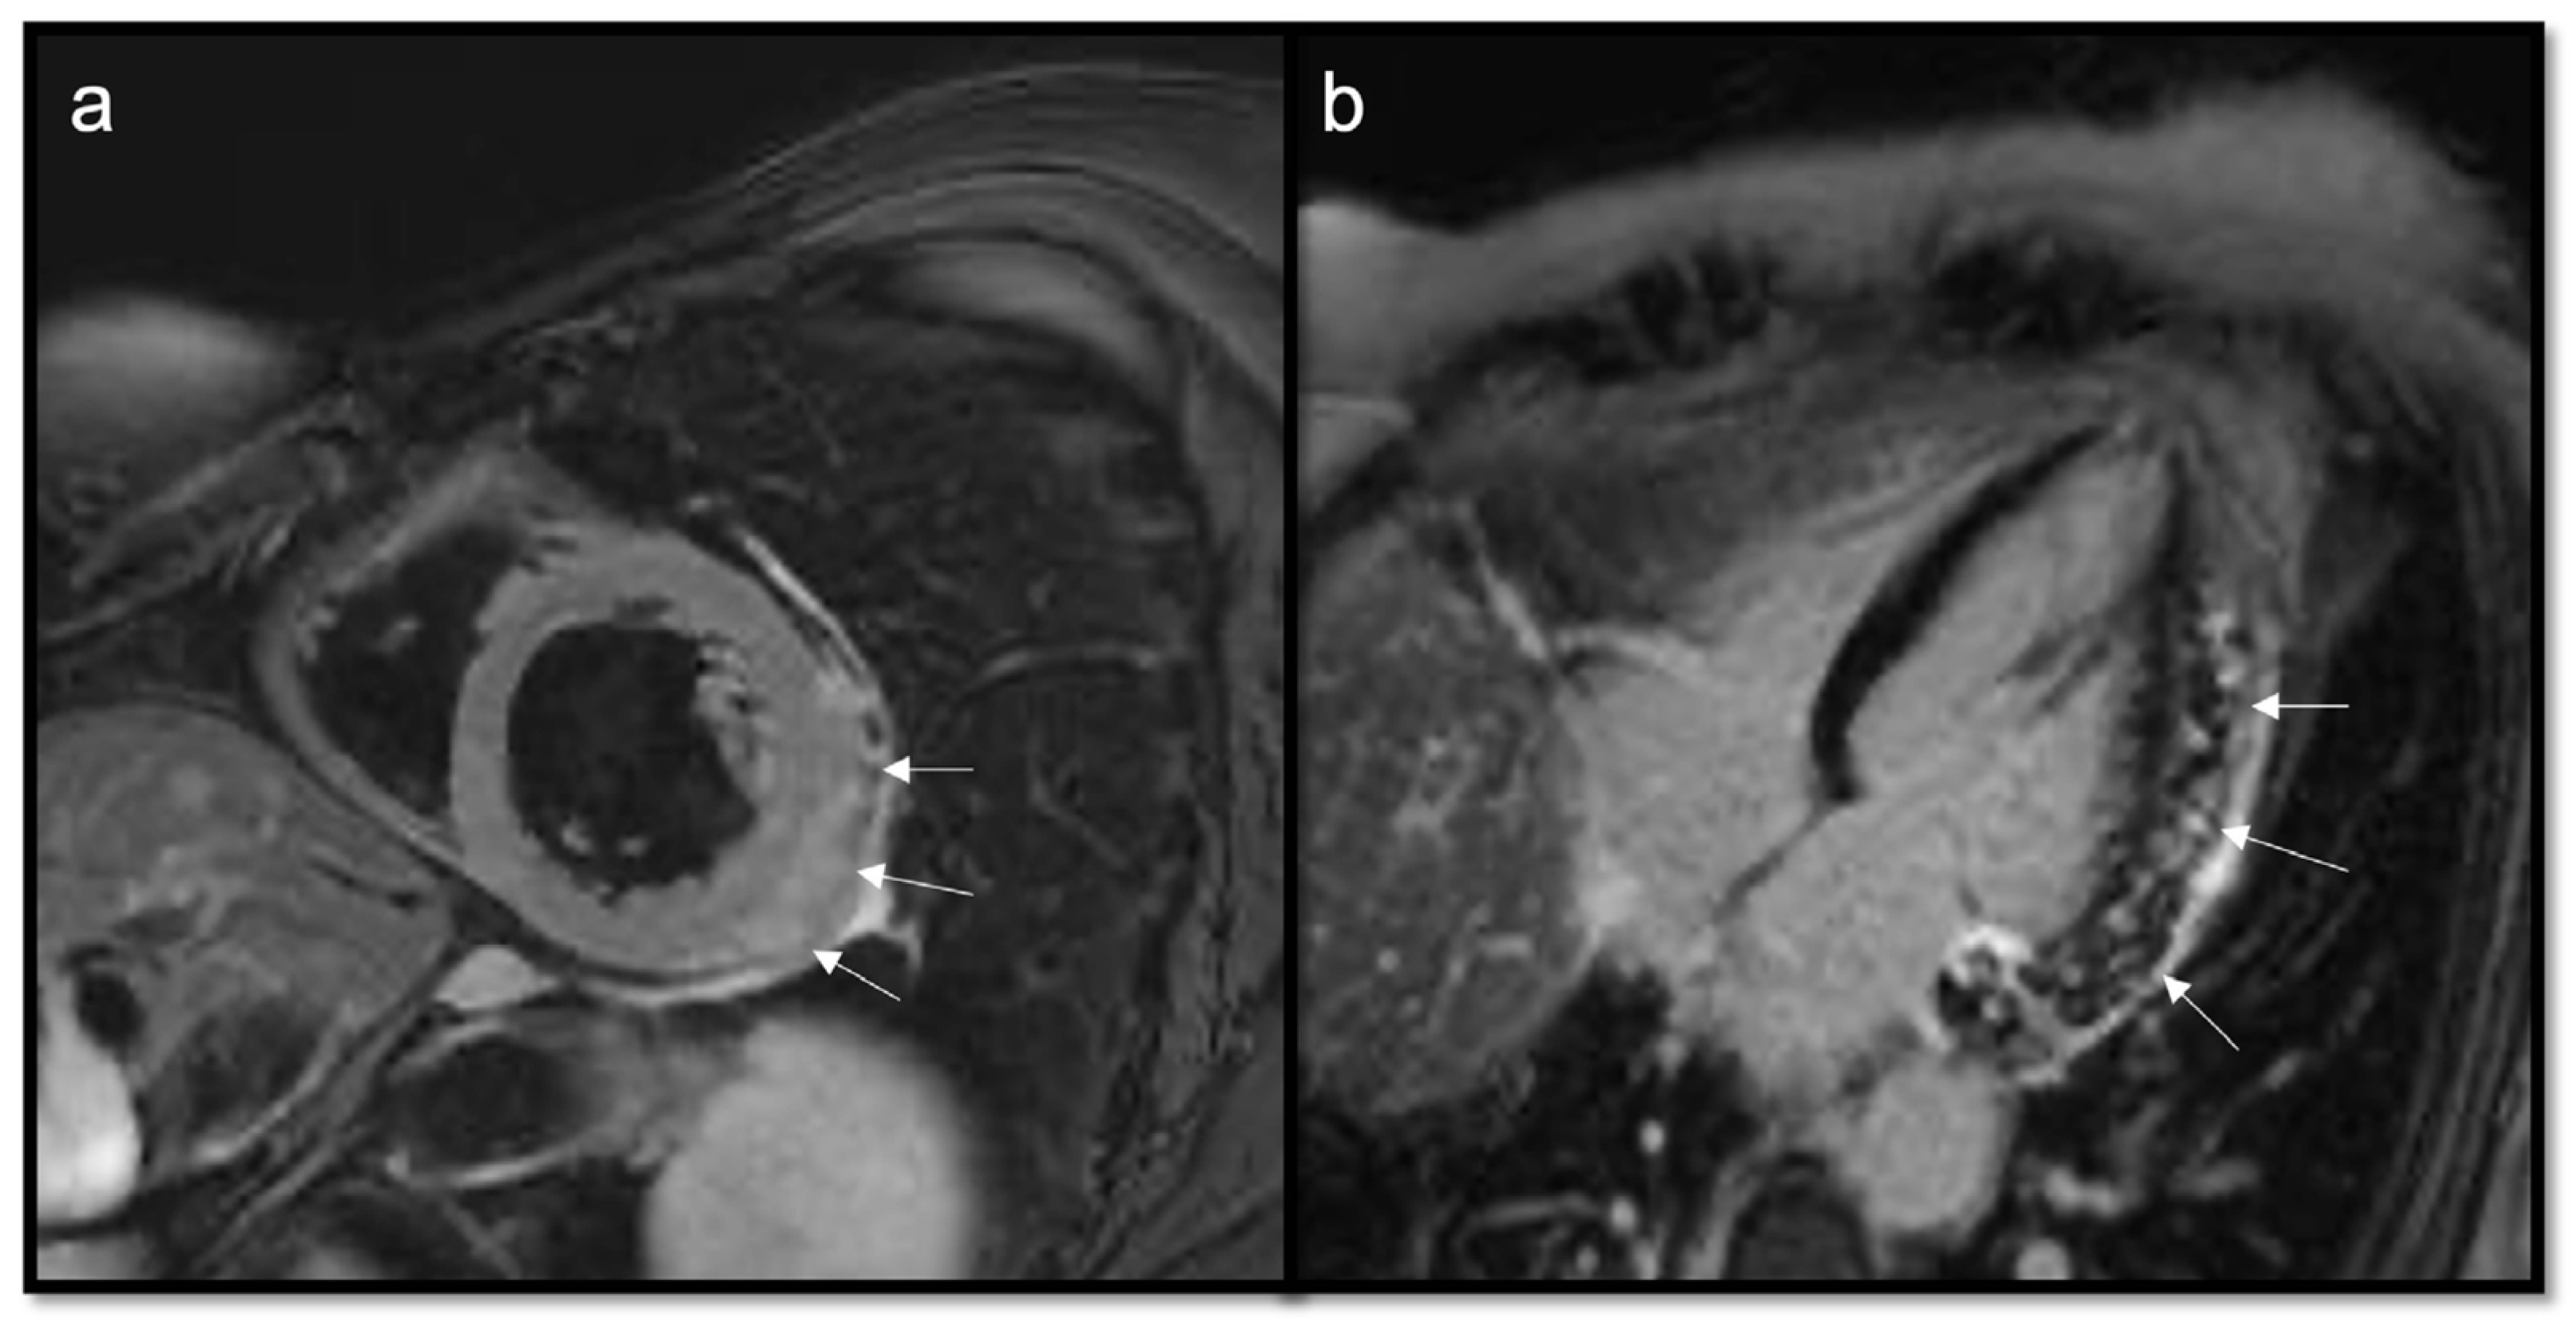

7.2.6. T1 and T2 Mapping

- Short T1/short T2 (as compared with the myocardium) for calcifications

- Short T1/long T2 for melanoma or lipomas and lipomatosis [64]

- Long T1/long T2 for most tumors, whether benign or malignant, with different degrees in particular for the T1 (close to the myocardium for rhabdomyoma, long or very long for myxomas [65] and fibroelastomas)

- T1 mapping allows for highlighting the difference between recent (<1 week) and old thrombi (>1 month), as recent thrombi have a significantly shorter T1.